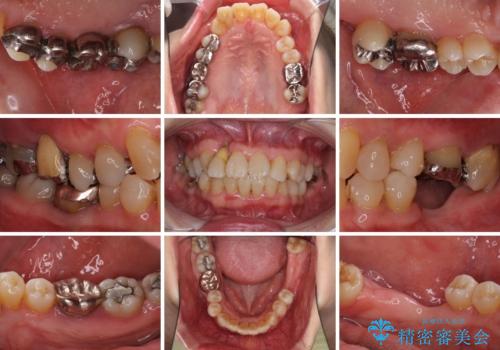

- 歯の欠損や歯肉からの出血などを気にして来院された患者様です。

診査の結果、歯周病であることが分かり、抜歯が必要な歯も見受けられました。

骨造成やインプラント、歯周外科、歯肉移植、矯正など、多くの処置を組み合わせて治療を行うこととしました。